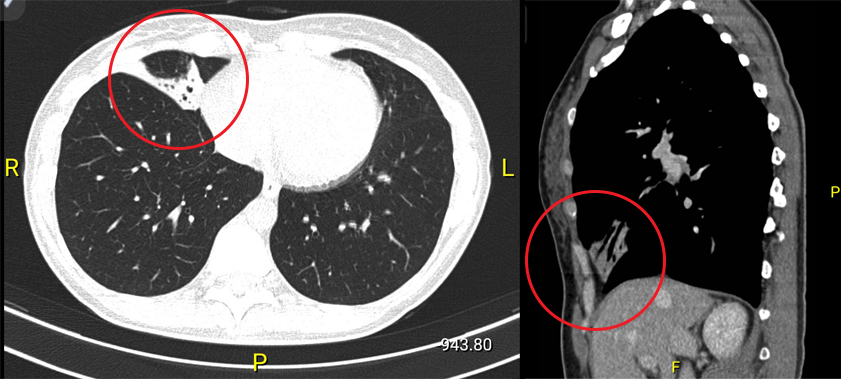

- Tomografia computerizata de inalta rezolutie (HRCT) a inlocuit bronhograma de contrast ca standardul de aur pentru diagnosticul imagistic al bronhiectaziilor. CT toracic poate detecta cu mare acuratete distributia modificarilor bronsiectatice. Anomaliile sugestive pentru bronsiectazie sunt reprezentate de dilatarea bronsica, astfel incat diametrul intern al bronhiei afectate este mai mare decat artera insotitoare. Extinderea bolii observata la examenul CT (HRCT) este corelata cu calitatea vietii si declinul functional respirator ulterior.